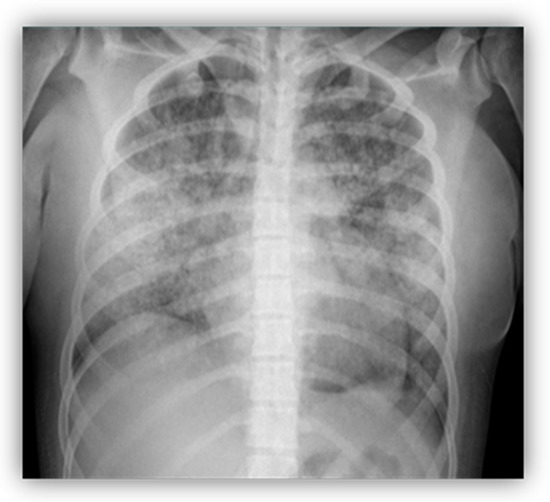

2.1. Case 1